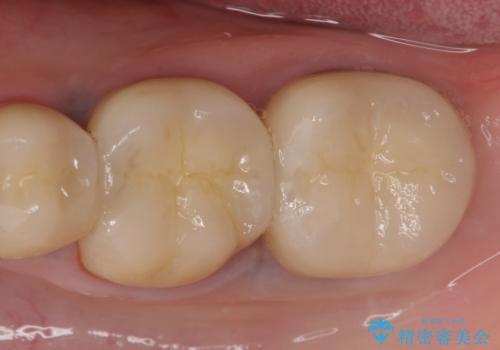

症状の消失を確認後、オールセラミッククラウンによる補綴を行いました。

今回用いたオールセラミッククラウンは、ジルコニアフレームという白い素材の上にセラミックを盛っているため審美性が非常に高いのが特徴です。

またジルコニアは人工ダイヤモンドの材料にも使われているほど高い強度を持っており、そのためオールセラミッククラウンは審美性だけでなく、奥歯やブリッジの補綴も可能とするクラウンです。